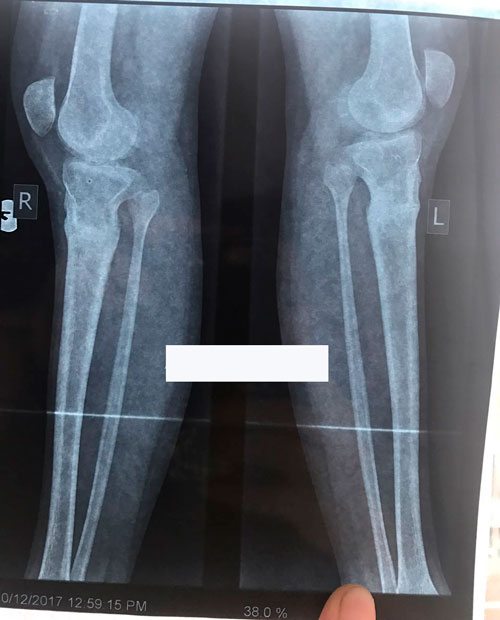

Исходник - 19 лет.

Дата операции 25.05.2017г.

Дата снятия аппаратов 10.08.2017г.

Срок лечения 75 дней.